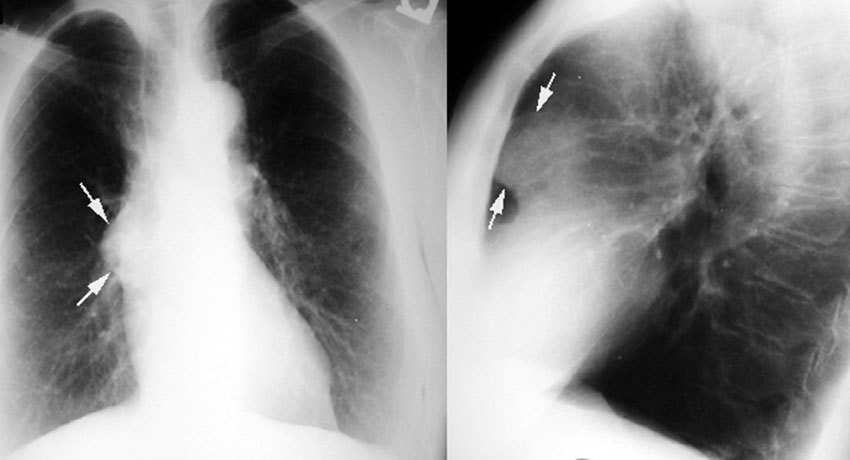

Большинство тимом можно обнаружить с помощью обычной рентгенографии. Опухоль выглядит как тень с ровными краями в верхней половине грудной клетки. Она частично перекрывает тень от сердца, находится преимущественно справа или слева.